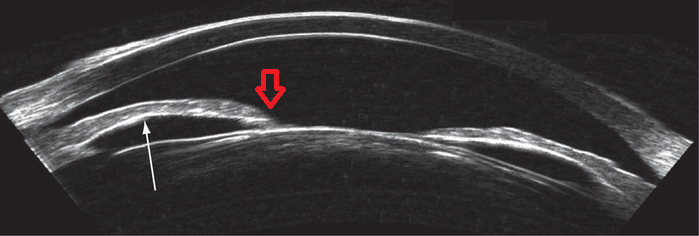

차단된 동공 이외에 전방과 후방사이의 연결 통로가 없게되면,

후방에서 전방으로 방수가 흘러나오지 못하고 후방에 점점 물이 고이게됩니다.

이는 홍채볼록(iris bombe)로이어지고, 이는 결국 전방각의 물리적 폐쇄(angle closure)로 이어집니다.

그래서 섬유주 절제술을 시행할 때, 주변부 홍채 절제술을 같이 시행하여,

홍채절제부위를 통해, 동공이외에 전방과 후방사이의 연결 통로를 만들어 주어,

수술후 염증발생으로 인한 동공차단을 예방하기 위함입니다.

하지만 이 홍채절제술 부위가 제대로되지 않았거나

홍재절제술이 시행되었더라도, 염증물질이나 유리체에 의해서 막힌경우에는,